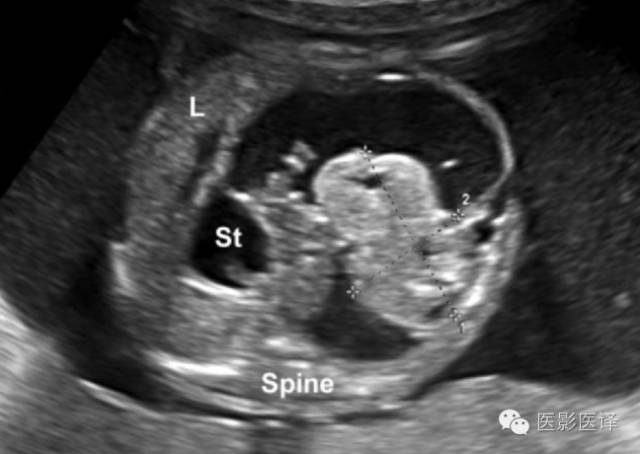

胎儿卵巢囊肿5.6厘米会消失吗,卵巢巨大囊肿与妊娠鉴别

图20.寄生胎。23周胎儿超声横断面显示一个长约36mm的半囊半实性包块(标尺标示)。肿物邻近脊柱,将胃(St)推挤至中线右侧,肝脏(L)向上移位。包块的位置及胃移位的方式表明其来源于腹膜后。卵巢囊肿不太可能在这个阶段的孕期出现。